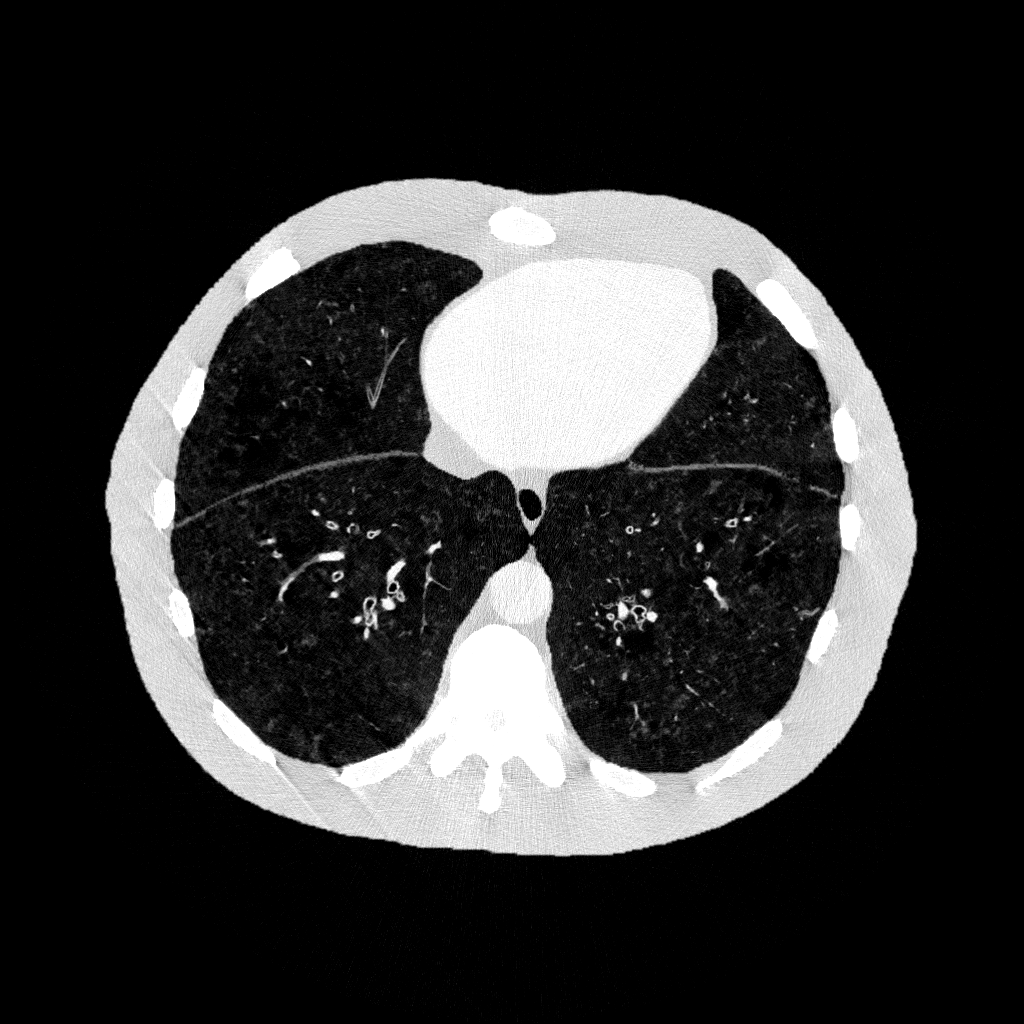

Example datasets: axial cross-sectional 3D CT images of a digital human phantom with COPD, generated using DukeCounter photon-counting CT scanners

Images from GaAs-based DukeCounter Scanner